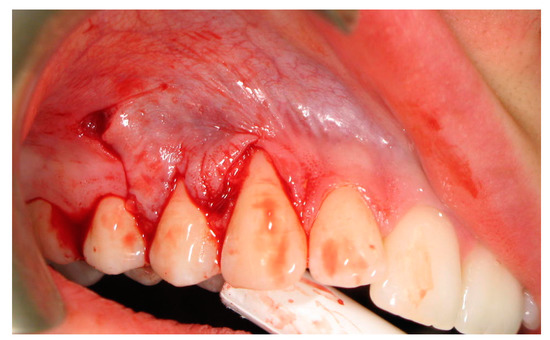

2.3. Surgical Procedures